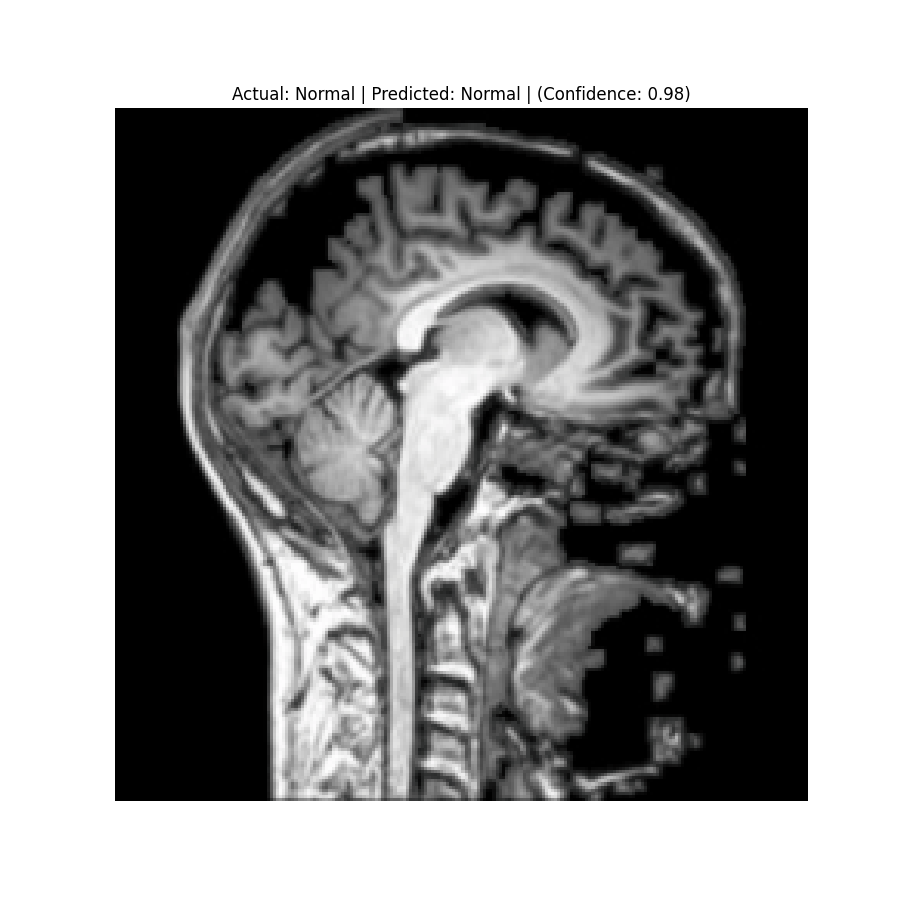

The dataset used in this project is the Brain Tumor Classification (MRI). It consists of MRI scans categorized into four classes: 👇

Glioma Tumor | Meningioma Tumor |

Normal | Pituitary Tumor |

Results

Check the predictions in the predictions folder. Below are some sample results:

![]() Actual: Normal Predicted: Normal (Confidence: 0.98) | ![]() Actual: Pituitary Tumor Predicted: Pituitary Tumor (Confidence: 0.99) |